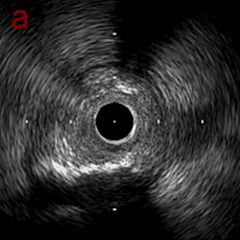

PreのIVUSではaの部位のみlipid plaqueを認め削ることでdistal embolismのリスクがあり、そのほかは270度の偏心性石灰化であるがwire biasは良好。

OAS low speedによる引きのsandingを3回行いIVUSを確認するとa-cでは心筋側側へのOASによる良好なbias変化と、それに伴いdの健常側への危険なbias変化を認めた。